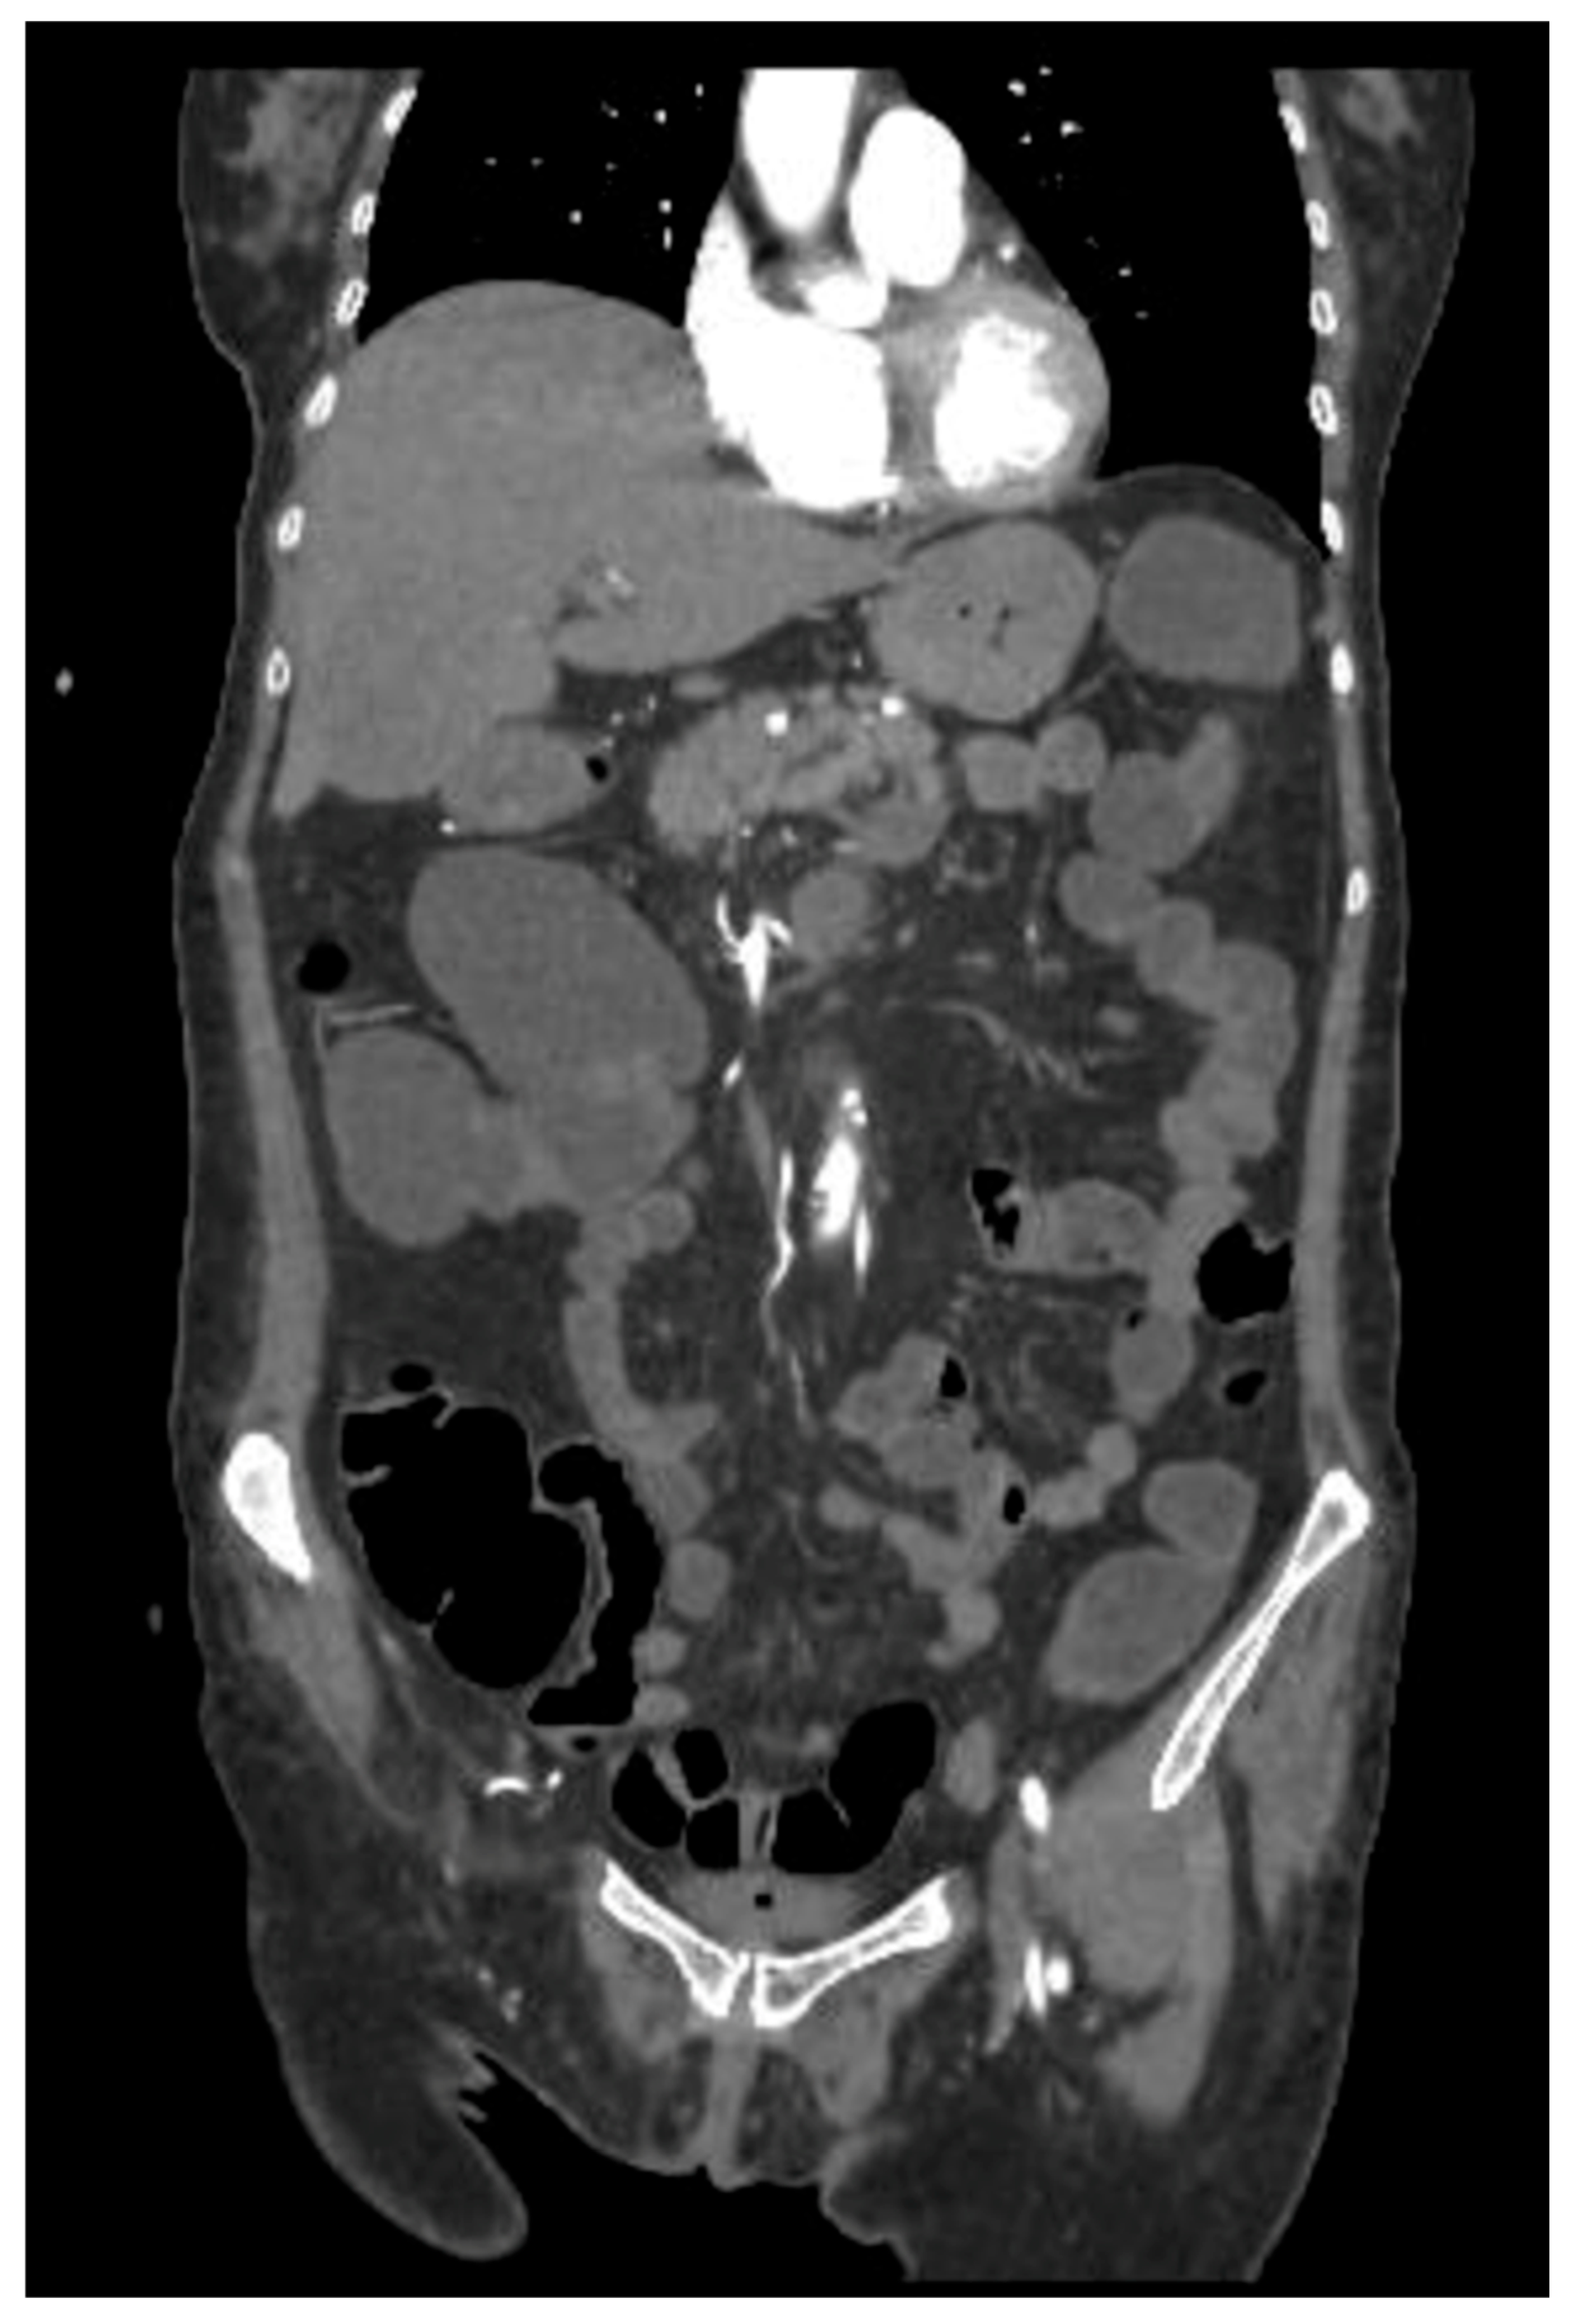

Three weeks later, however, the patient underwent ocular evisceration due to corneal perforation secondary to corneal melting. HLA typing (including HLA-A29, HLA-B27, and HLA-DR4) was not performed. Corneal scraping and culture were also not carried out prior to surgical intervention. Due to persistent diarrhea and the suspicion of a toxic megacolon, an abdominal CT was performed, revealing intestinal pneumatosis with signs of vascular hypoperfusion in the transverse colon (Figure 2). An exploratory laparoscopy was performed, but there was no evidence of ischemic damage.

Figure 2. CT scan with contrast medium: hypoperfused appearance of the walls of the transverse colon, with the presence of free air in the context of the walls and around the viscera, as in intestinal pneumatosis.